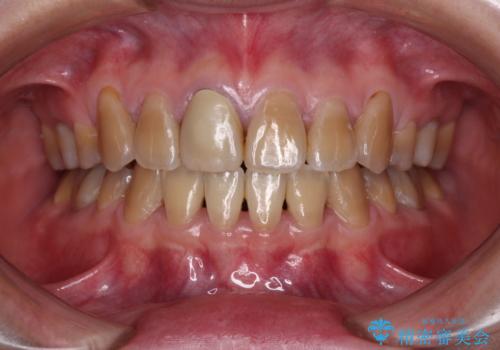

- 前歯の叢生と、奥歯の咬み合わせの悪さを気にして来院された患者様です。

左下には後続永久歯の欠損した乳歯が残存しており、叢生を相まって咬合関係が乱れていました。

乳歯は抜歯し、インビザラインにて矯正治療を行いながら、並行してインプラントによる補綴治療を行うこととしました。